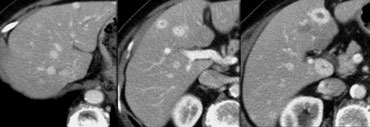

Adenomas in arterial, portal venous and equilibrium phase Adenomas in arterial, portal venous and equilibrium phase

Adenoma

On the left two incidentalomas.

Decide for yourself why these are not FNH lesions.

In the arterial phase there are two hypervascular lesions, somewhat less dense than we would expect in FNH.

Both lesions demonstrate a halo of a capsule, which should not be apparent in FNH.

Unlike in FNH, the enhancement is inhomogeneous and in the portovenous and equilibrium phase the lesions are not isodens to the liver.